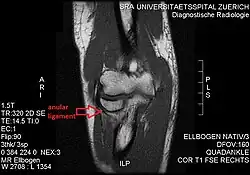

T1 weighted MRI showing the anular ligament -